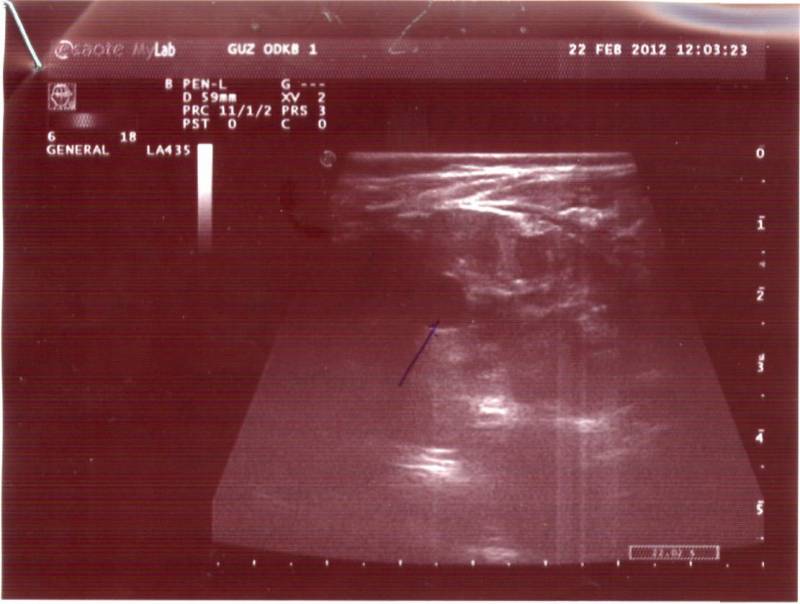

Здравствуйте. Моей дочке 10 месяцев. В месяц сделали УЗИ - поставили диагноз "простая солитарная киста". В дальнейшем находились под наблюдением нефролога и делали несколько УЗИ. На сегодняшни й день ставят диагноз "поликистоз, вторичный пиелонефрит". По анализу крови креатинин 29,4, мочевина 2,8. Напишите, пожалуйста, можно ли по снимкам определить вид поликистоза: детский или взрослый. Снимки выкладываю. Буду благодарна за высказанное мнение.

Похоже на взрослый поликистоз - но, конечно смотреть надо при лучшем разрешении, т.е. за экраном и важно знать ещё ряд параметров : 1) сколько кист в каждой почке, 2) их размер, 3)размер каждой почки, 4) есть ли изменения в печени.

Думаю. что необходимо сделать УЗИ в том медучреждении, где имеется нефрологическое отделение и детские нефрологи и затем очно проконсультировать с нефрологом - попросите, что бы врач, делающий УЗИ, распечатал картинку правой и левой почки - если Вы разместите здесь- фото или скан УЗИ-изображения - можно будет более предметно высказаться.